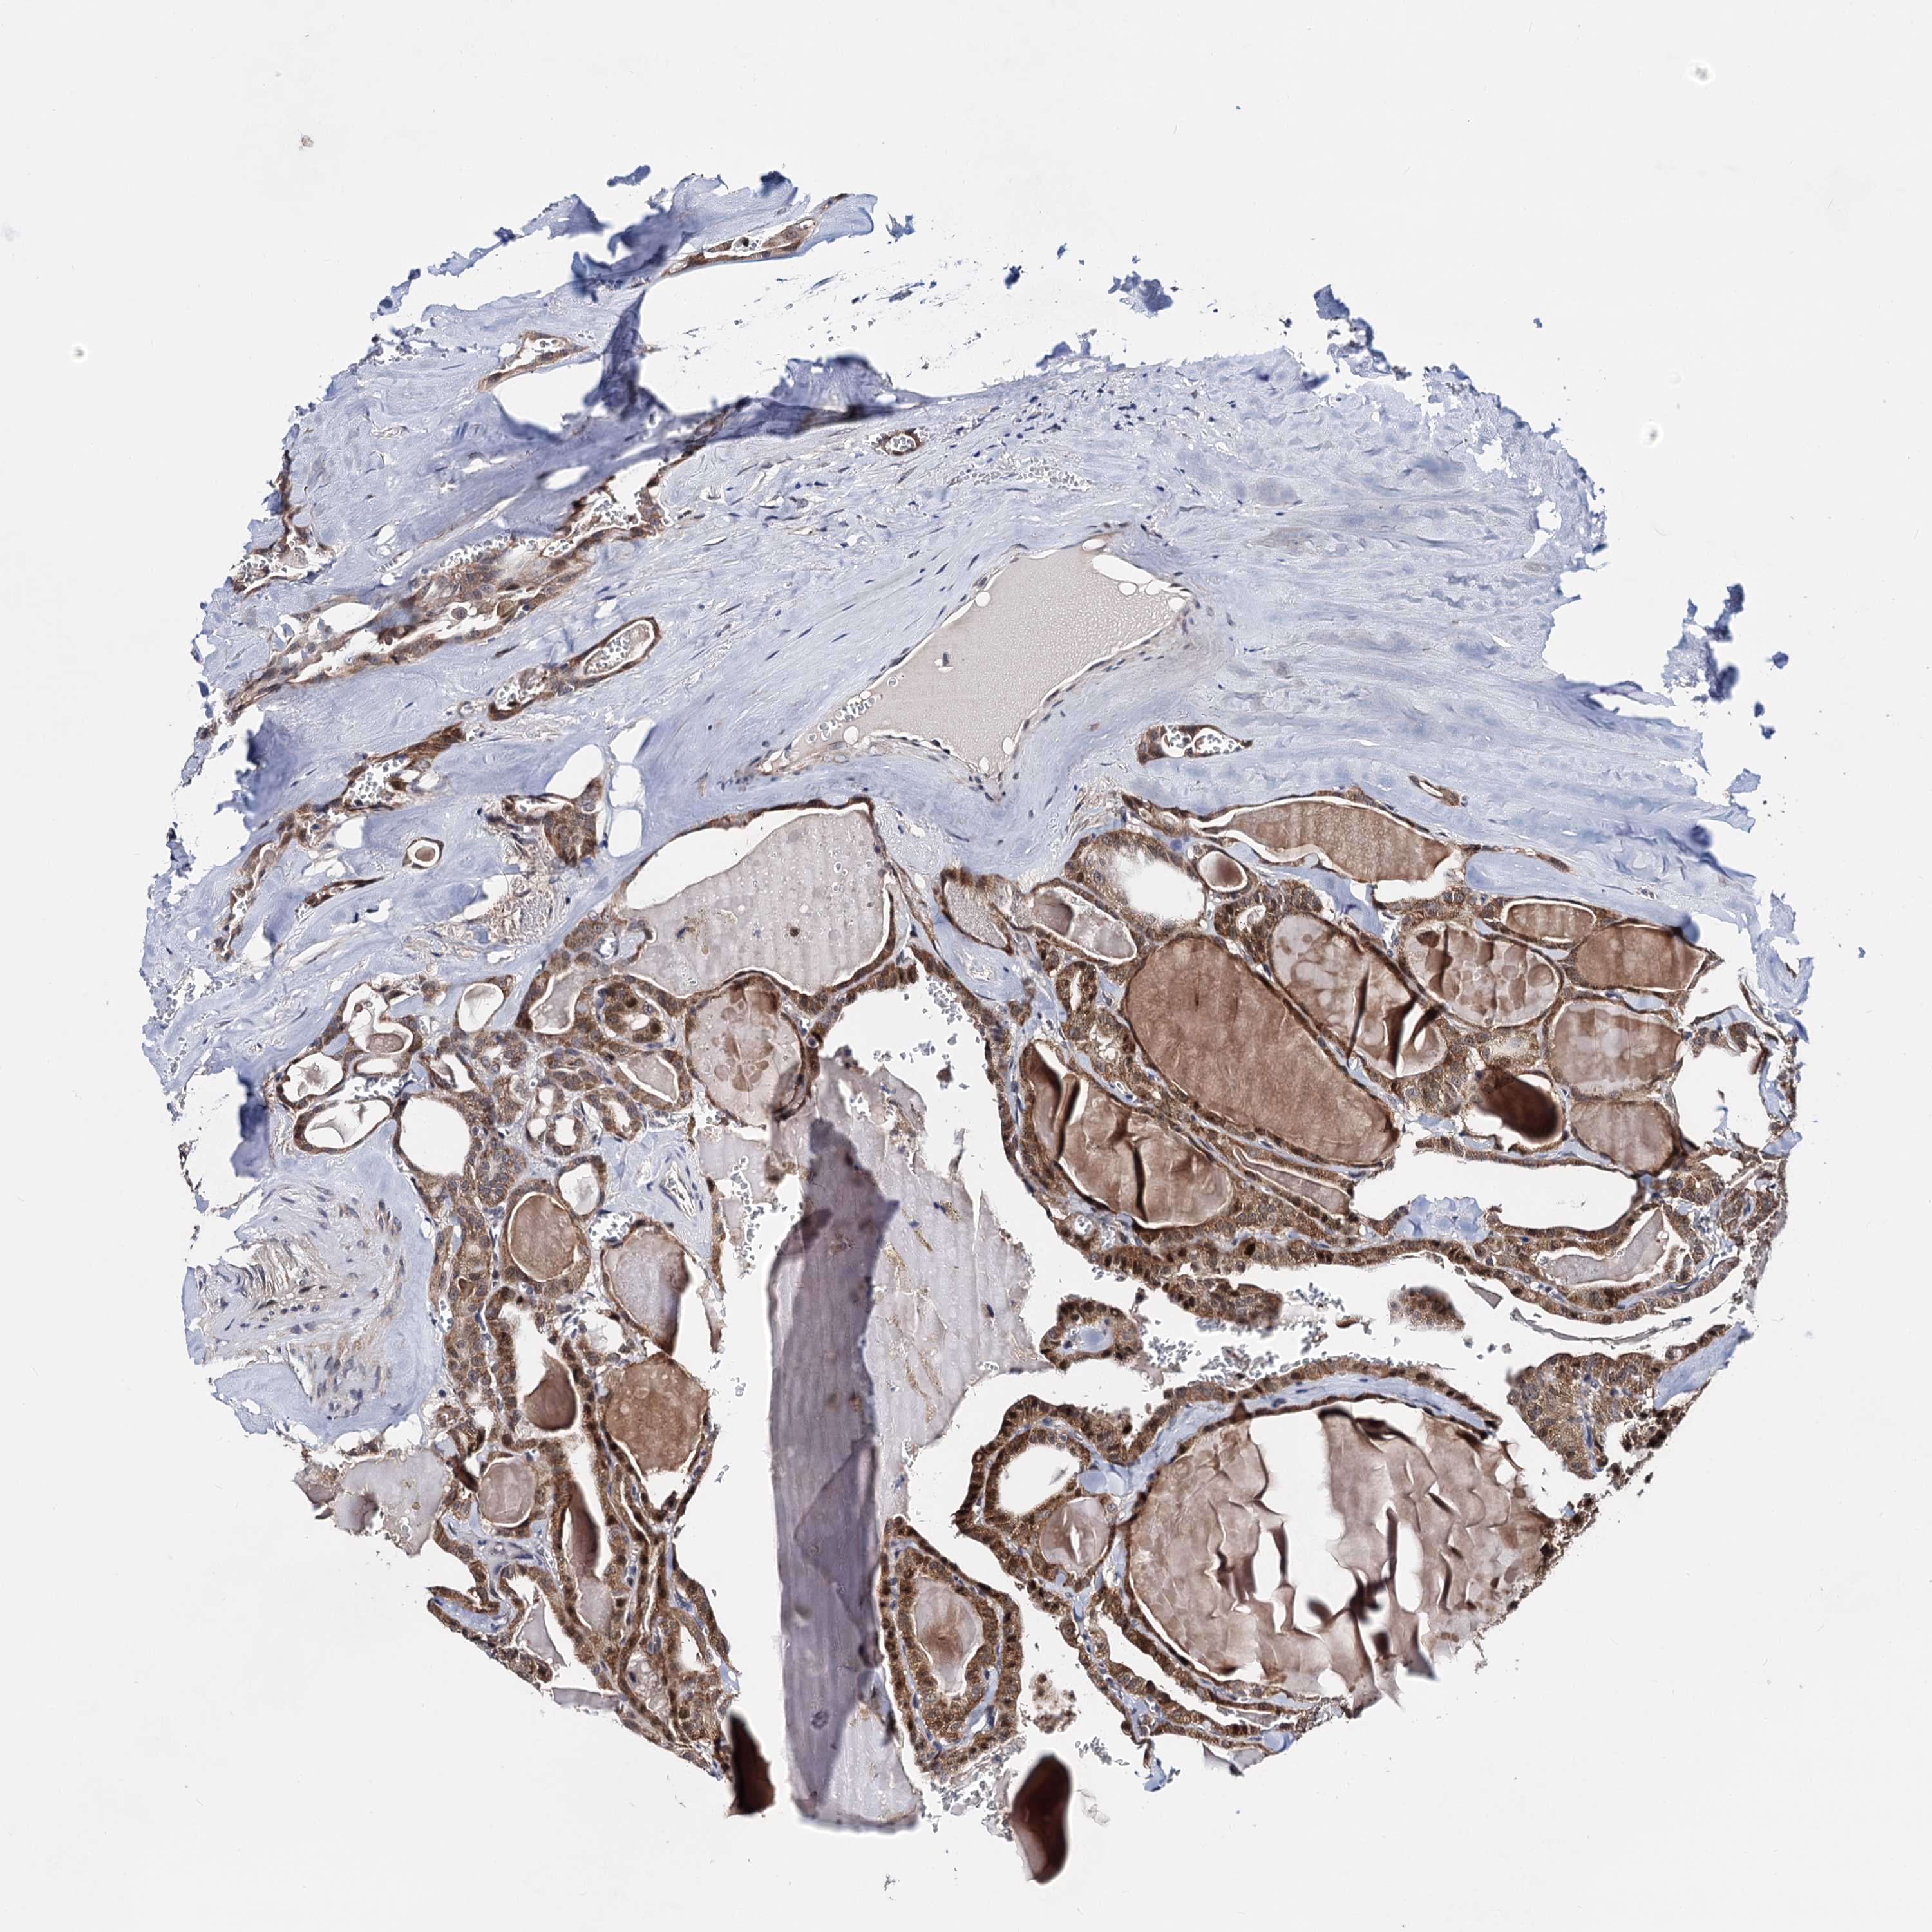

THYROID CANCER - Protein expressioni

A mouse-over function shows sample information and annotation data. Click on an image to view it in a full screen mode. Samples can be filtered based on level of antibody staining by selecting one or several of the following categories: high, medium, low and not detected. The assay and annotation is described here.

Note that samples used for immunohistochemistry by the Human Protein Atlas do not correspond to samples in the TCGA dataset.

Antibody stainingi

Antibody staining in the annotated cell types in the current human tissue is reported as not detected, low, medium, or high, based on conventional immunohistochemistry profiling in selected tissues. This score is based on the combination of the staining intensity and fraction of stained cells.

Each image is clickable and will lead to virtual microscopy that enables deeper exploration of all samples and also displays staining intensity scores, fraction scores and subcellular localization as well as patient and tissue information for each sample.

Antibody HPA040126

Staining

High

Medium

Low

Not detected

Intensity

Strong

Moderate

Weak

Negative

Quantity

>75%

75%-25%

<25%

None

Location

Nuclear

Cytoplasmic/membranous

Cytoplasmic/membranous,nuclear

Papillary adenocarcinoma, NOS

Follicular adenoma carcinoma, NOS